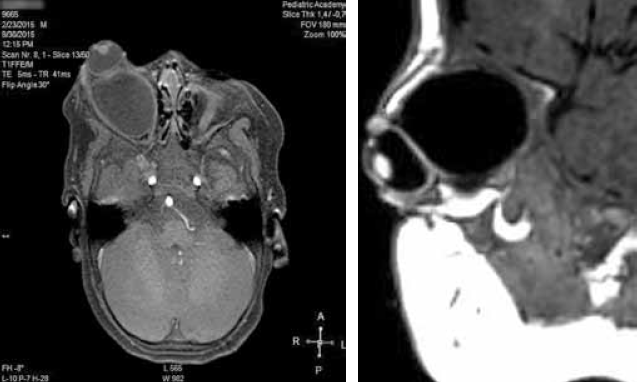

Была заподозрена киста зрительного нерва, которая и была выявлена при магнитно-резонансной томографии глазниц и черепа (рис. 3). По-видимому, она и явилась причиной дислокации глазного яблока и некоторого ограничения его подвижности.

Рис. 3. Результат МРТ глазниц ребенка А. Определяется киста в мышечной воронке левой глазницы с жидким содержимым

Магнитно-резонансная томография (рис. 6) подтвердила наличие патологического объемного образования правой глазницы. Изменений головного мозга не выявлено.

Рис. 6. Результат МРТ глазниц ребенка М. Определяется объемная киста с гомогенным жидким содержимым, заполняющая правую глазницу, смещающая и деформирующая правое глазное яблоко